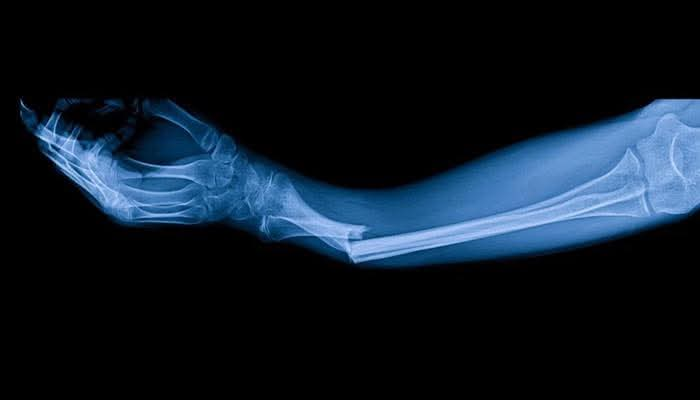

چینی محققین نے ایک ایسا بریک تھرو گلو بنایا ہے جسے “Bone 2” کا نام دیا گیا ہے، جو ٹوٹی ہوئی ہڈیوں کو صرف تین منٹ میں ٹھیک کرنے کی صلاحیت رکھتا ہے۔ سمندری مخلوق کے قدرتی چپکنے سے متاثر ہوکر، گوند ہڈیوں کو محفوظ طریقے سے جوڑتا ہے، جسم میں جذب ہوجاتا ہے، انفیکشن کے خطرے کو کم کرتا ہے، اور اضافی سرجری کی ضرورت کو ختم کرتا ہے۔ 150 سے زیادہ مریضوں پر کامیاب تجربہ کیا گیا۔